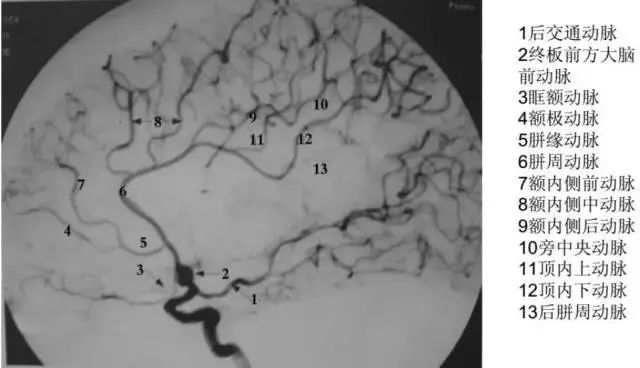

大脑前动脉(ACA)是颈内动脉的主要分支之一,是供应大脑半球内侧的主要动脉。ACA经胼胝体膝部至其背侧面,沿胼胝体沟向后穿行至胼胝体压部稍前方,并分出终末支。见下图。

A2段,即垂直段:为前交通动脉至胼胝体膝部下方的一段,侧位片上呈由后下向前上方走行,略成“S”形。正位片上显示为沿中线垂直上行,故又称垂直段。

A3段,即膝段:以额极动脉与A2段为界,与胼胝体的膝弯曲一致。

A4段,即胼周段:位于胼胝体沟内,也叫胼周动脉,分布于额叶。

A5段,即终段:为楔前动脉,分布于顶叶。